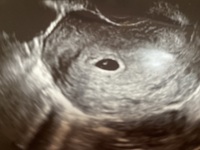

助産師さきの「いいママより、幸せなママになろう!」卵黄嚢が見えた!でも胎嚢は小さい

妊娠3ヶ月 妊娠8週 9週 10週 11週 妊娠初期 の超音波写真 妊娠 出産 育児に関する総合情報サイト ベビカム